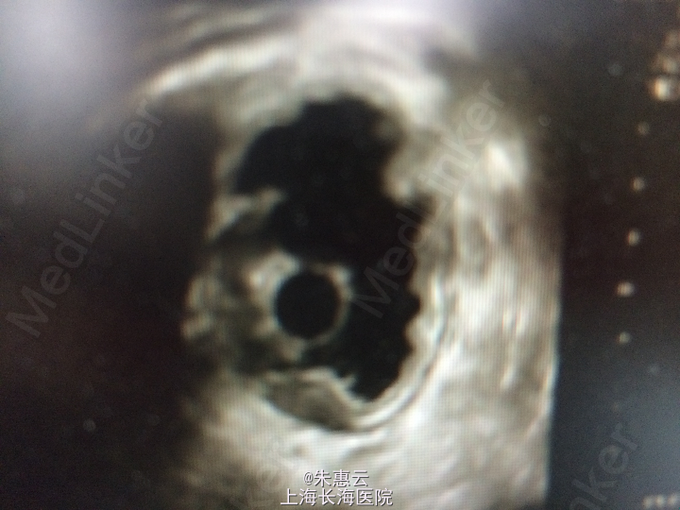

患者,男,61岁 主诉:上腹部不适2月 现病史:因牙痛自服消炎药(具体不详)后,出现上腹部不适,无压痛及放射痛,无发热,无呕血、黑便,就诊于我院行胃镜检查示:胃窦部粘膜隆起性质待查,糜烂性胃炎,十二指肠球部霜斑样溃疡。病理:(胃窦)中度慢性非萎缩性胃炎,HP(+)。超声内镜示:胃粘膜隆起性病变(畸胎瘤可能)。 既往史:2005年及2013年因“胃溃疡”出现黑便,当地医院给与止血、补液等治疗后,患者至今未发黑便。

专科检查:未见明显异常。 辅助检查:胃镜检查示:胃窦部粘膜隆起性质待查,糜烂性胃炎,十二指肠球部霜斑样溃疡。病理:(胃窦)中度慢性非萎缩性胃炎,HP(+)。超声内镜示:胃粘膜隆起性病变(畸胎瘤可能)。 住院期间主要检查结果:血、尿、粪三大常规,肝肾功能电解质、肿瘤指标等未见明显异常。

诊断:胃窦粘膜下隆起 诊疗经过:入院后行胃ESD术,术中于粘膜隆起区下方见较大溃疡,结合患者HP(+),故先行抗HP治疗。